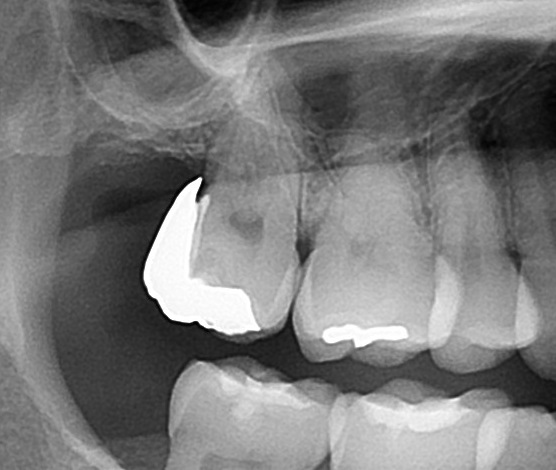

・ジルコニアインレーが合っていない

ジルコニアインレーを入れてもらうも、歯ブラシが引っかかり、冷たいものがしみて痛いという患者さん。

一番奥の歯に白いジルコニアインレーが入っている。

エックス線写真で歯の中を検査してみると、

ジルコニアインレーが大きく作られており、歯との間に隙間が出来ている。ここに歯ブラシの毛先が引っかかり、冷たいものが入ると痛む原因。

こちらは担当医と、製作した歯科技工士の技術力による不具合。

さらに、治療のためにジルコニアを外してみると、

ジルコニアインレーの下に虫歯が残っている。